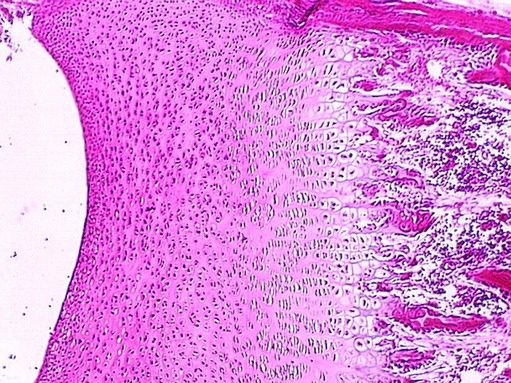

Higher magnifications of the resting zone (top) and the

zone of proliferation (bottom) are shown in this photo. The zone of proliferation is responsible for the growth in length of long bones.